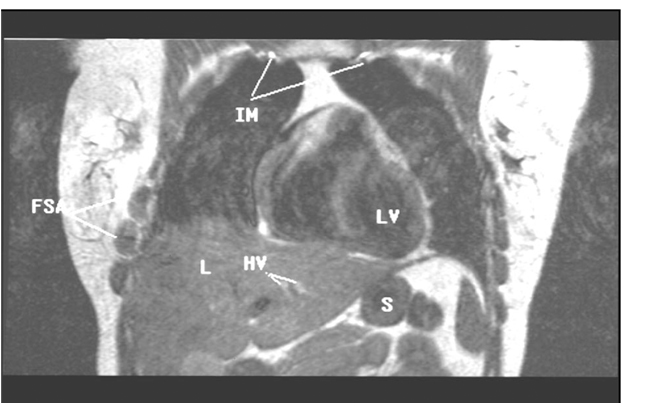

Figure 8: This is an anterior image of the coronal abduction external rotation of the upper extremities sequence in Figure 7. This image displays high signal intensity (white) internal mammary (IM) and hepatic veins (H) reflecting increased thoracic and abdominal pressure secondary to decreased venous return on a T-1 sequence. First fascicle of the serratus anterior muscle (FSA), liver (L), left ventricle (LV), stomach (S). With permission from James D. Collins, MD. Read complete article here.